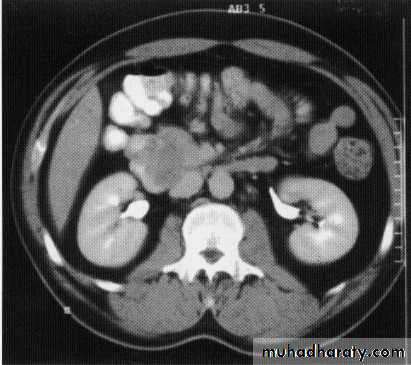

Ct scan carinal LAP